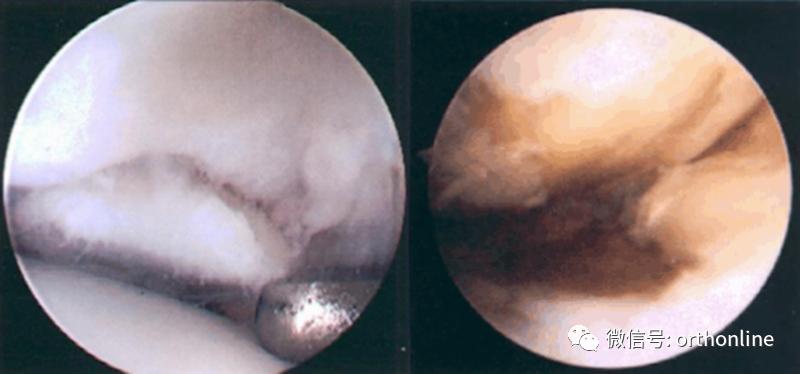

髌骨软化症Ⅲ级

髌骨软化症Ⅳ级